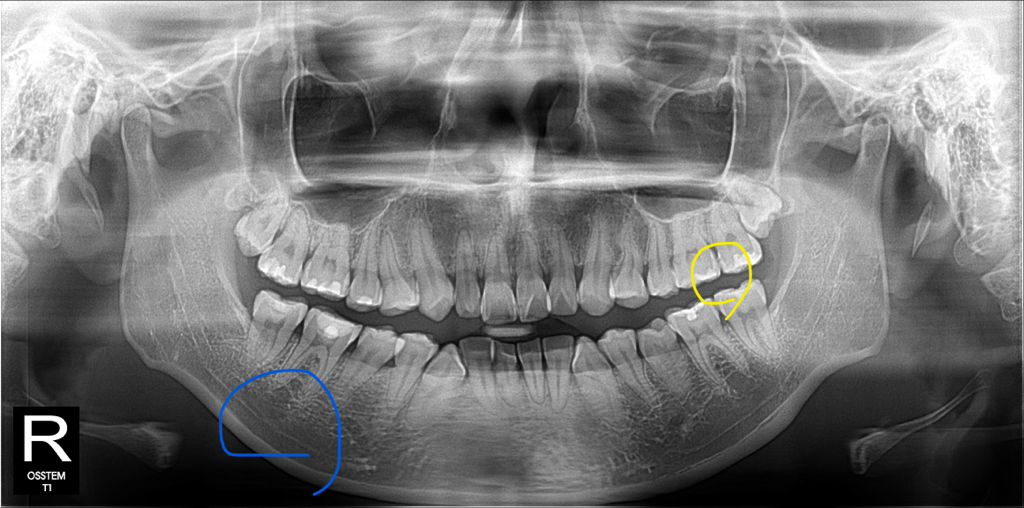

노란색 동그라미 친 부분입니다

• 1번 째 사진

저정도의 상태라면 제거하지 않고 관리하면서 지켜보실꺼 같습니다. 어쨋든 인레이를 제거하는거 자체가 치아의 손상이라서 신경치료를 해야될 가능성이 높습니다.

추가금액에 대해서는 직접 문의를 해보셔야하며 아마 내실 가능성이 높습니다. 치료는 하시는게 맞아보입니다